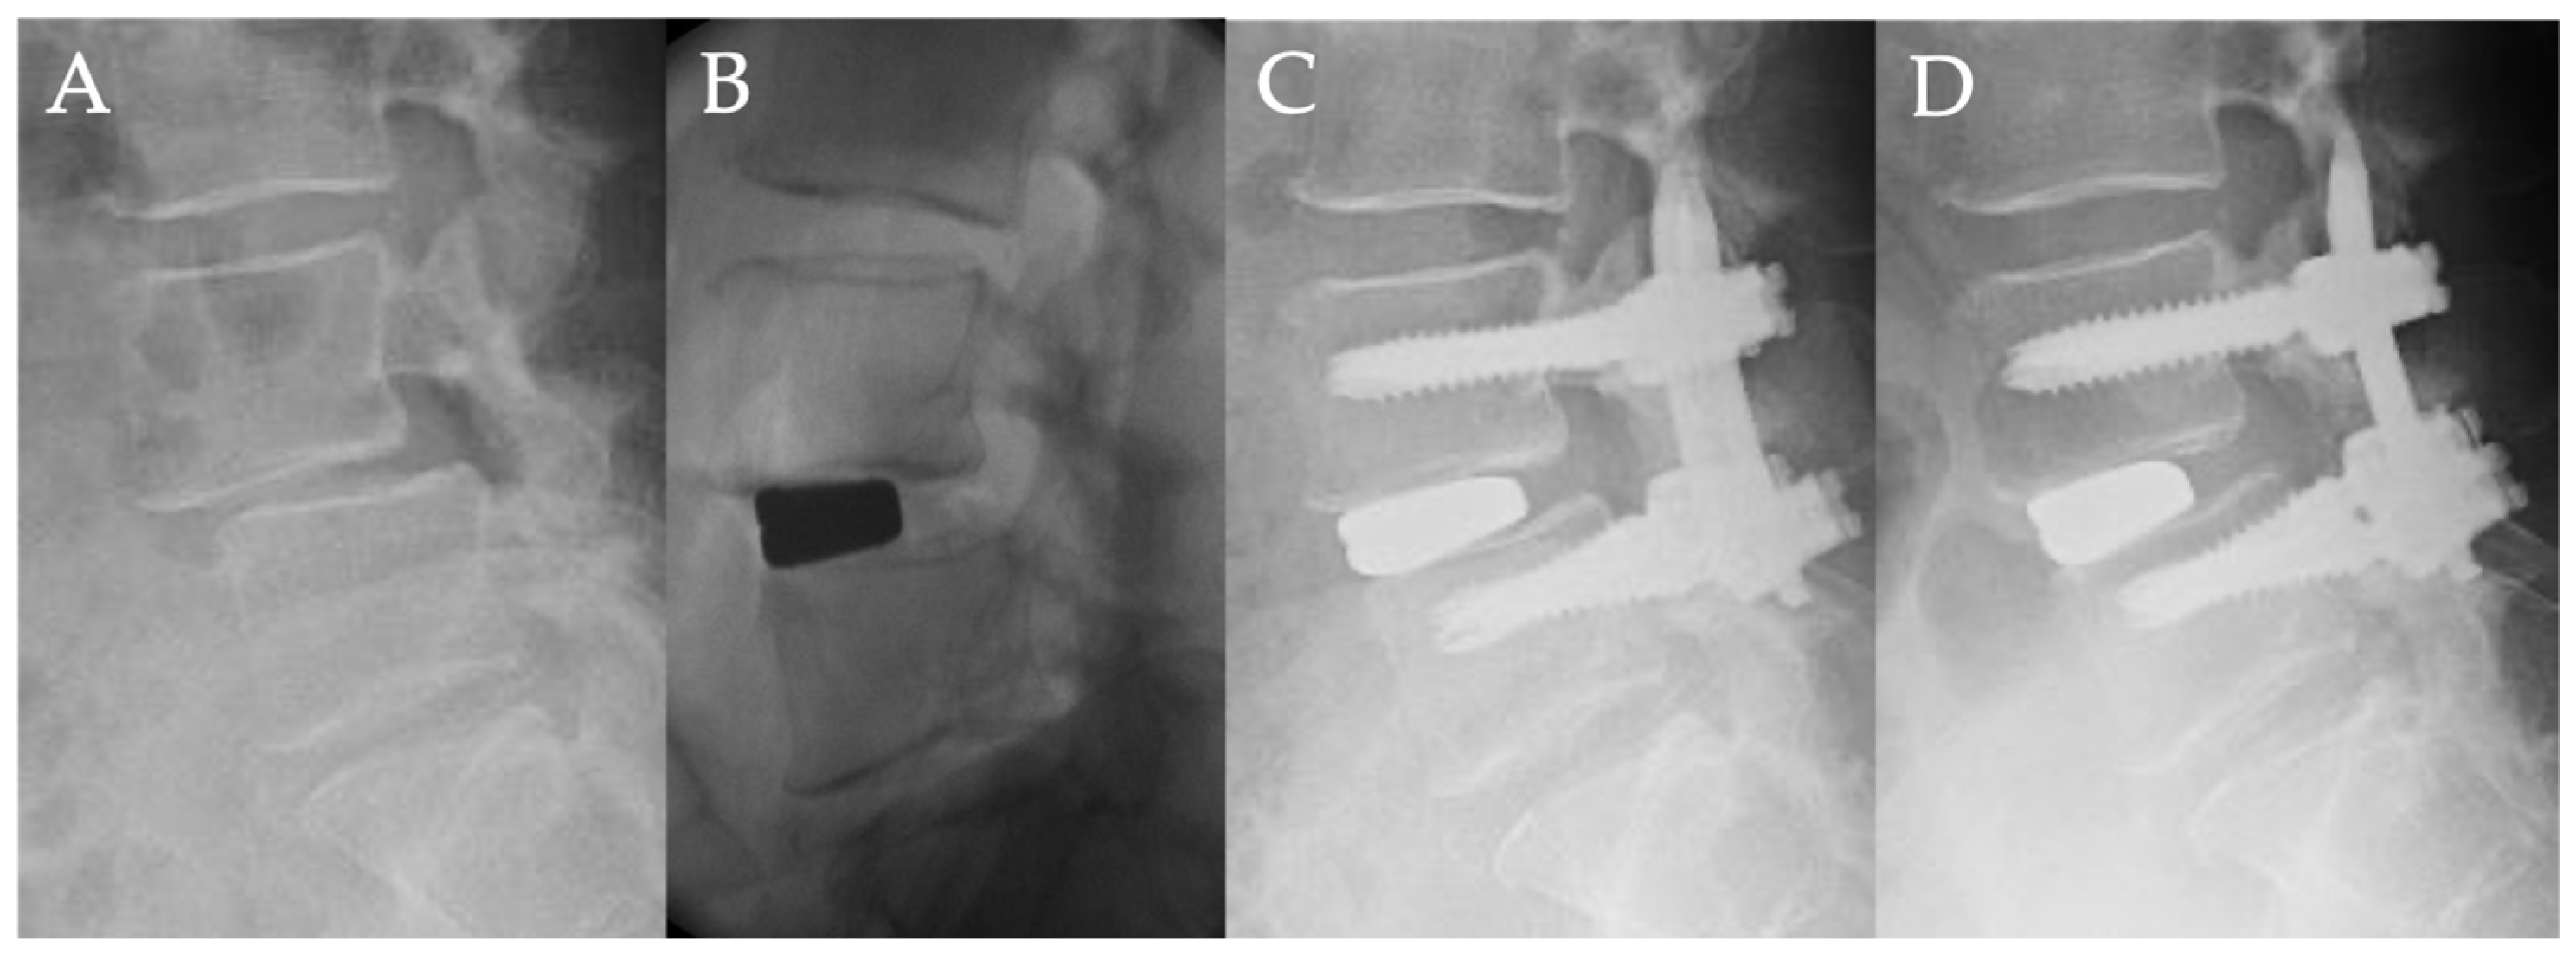

Case Presentation